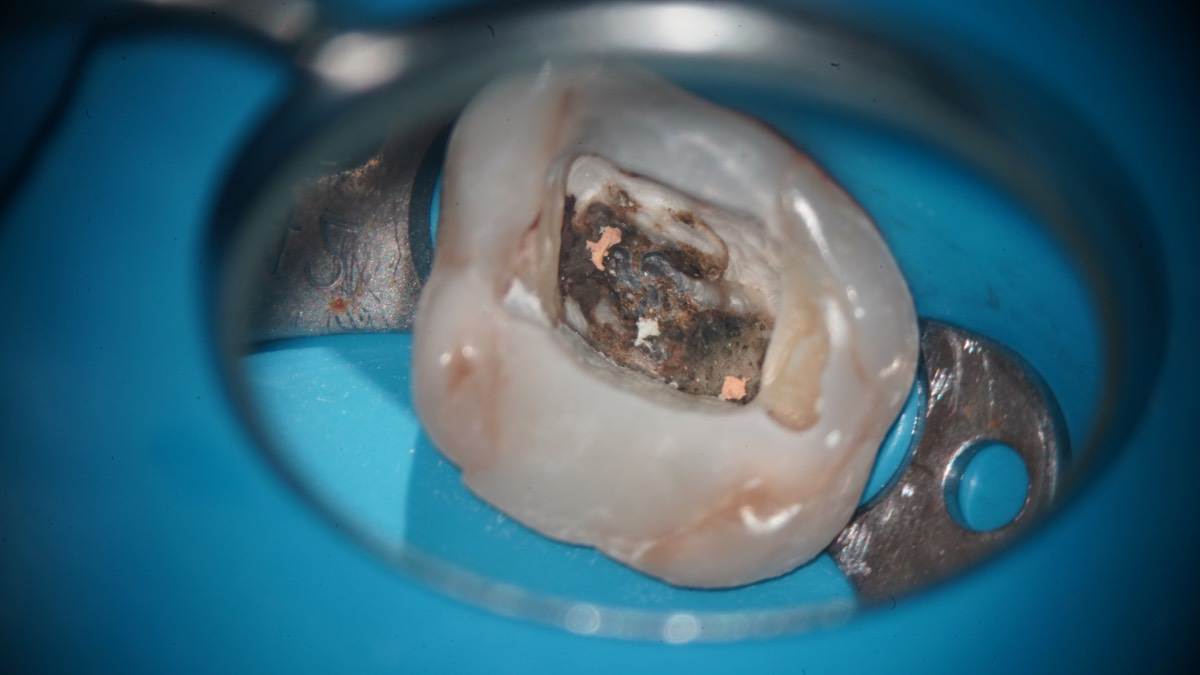

Гарриевич Опубликовано 31 января Автор Поделиться Опубликовано 31 января Когда в твоем кресле оказывается пациент с редким заболеванием «стоматолог-терапевт» работать всегда… легче. Именно! Потому что ты на 100% уверен, что этот человек понимает разницу между «гарантия» и «прогноз», а он на 100% уверен, что ты тот кто ему нужен. Зуб 4.7 со сложной анатомией, ступенькой в мезиальной системе, двойным изгибом, пропущенным каналом и апикальным периодонтитом. Реколл 1 год И сам осмотр через 1 год 4 1 1 Ссылка на комментарий

Гарриевич Опубликовано 7 апреля Автор Поделиться Опубликовано 7 апреля Извлечение двух фрагментов сломанных инструментов из одного зуба:) И если кому интересно, то вот полный фотопротокол 3 Ссылка на комментарий